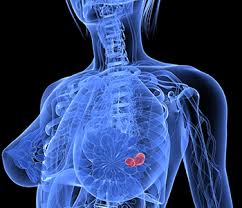

Benign, noncancerous masses can appear as a focal asymmetry. Breast cancer can present either as an area of focal asymmetry or when advanced can even present as a new asymmetry in breast size. Images are displayed as a series of thin slices that can. The outer edges of these cells look fuzzy or spiky (called spiculated). What does breast cancer look like on a mammogram? Diagnostic mammograms involve taking more views than screening mammograms. What does breast cancer look like on a mammogram? Not all women have calcifications in their breasts—but most do. This is why you should always talk to your doctor if you notice an unexplained change in the size of a breast. Ultimately, the news is good: Rather than an image that is formed from pictures taken from top to bottom and side to side like a. Even if you have a lump in only one breast, pictures will be taken of both breasts. They will look carefully at the mammogram to interpret the results.

That makes it easy to detect abnormalities, which generally show up as white. The look of breast cancer on a mammogram a tumor or lump will appear as a focused white area on the mammogram. Breast cancer can present either as an area of focal asymmetry or when advanced can even present as a new asymmetry in breast size. This is why you should always talk to your doctor if you notice an unexplained change in the size of a breast. However, in rare cases, breast cancer can be the cause of gynecomastia so, a full mammographic investigation is always necessary. Treatment typically involves some type of surgery and depends upon the staging of the. We'll show you breast cancer pictures to help you identify any physical traits of the condition. 3d mammography is capable of producing more detailed.